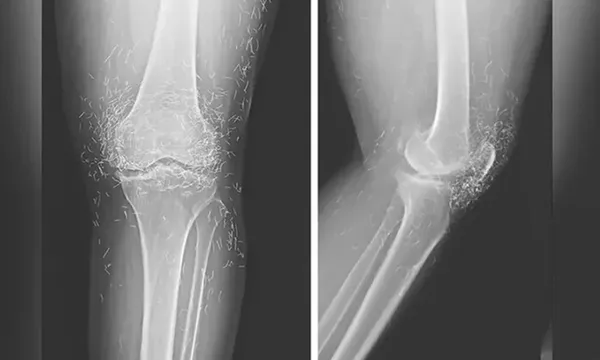

Kết quả chụp X-quang cho thấy phần bên trong xương chày dày lên và cứng lại, các khối u xương ở đầu gối, tất cả đều là các triệu chứng thường gặp của viêm xương khớp – nhưng cũng có hàng trăm sợi chỉ vàng nhỏ xíu cắm vào mô quanh đầu gối.

Các bác sĩ cảnh báo rằng châm cứu bằng chỉ vàng chưa được khoa học chứng minh mang lại lợi ích cho bệnh nhân, nhưng lại tiềm ẩn nhiều rủi ro đã biết. Những sợi chỉ nhỏ xíu này có thể gây u nang, di chuyển vào cơ thể và làm tổn thương các mô xung quanh, nhưng chúng cũng có thể khiến việc chụp MRI có khả năng cứu sống bệnh nhân trở nên bất khả thi do nguy cơ kim loại bị dịch chuyển và tổn thương mạch máu.